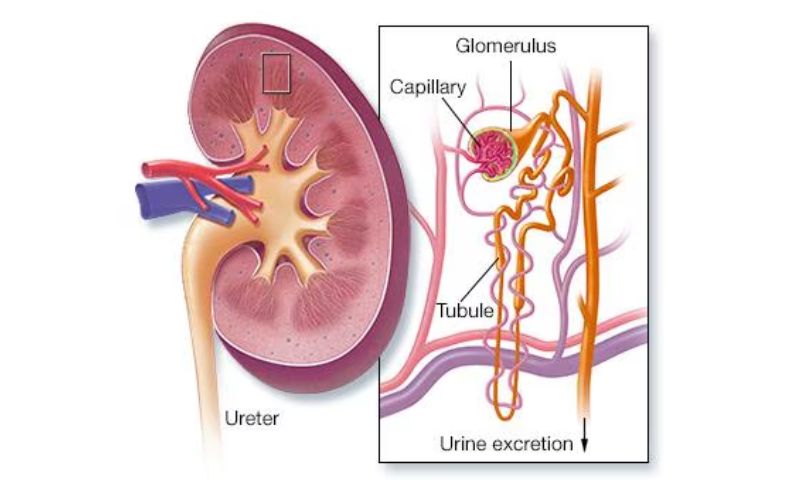

Acute and chronic kidney diseases

Kidney diseases are categorized into two types: acute and chronic, both requiring timely diagnosis and management to maintain optimal kidney function.

Nephrotic syndrome

Nephrotic syndrome is a kidney disorder characterized by the loss of large amounts of protein in the urine (proteinuria), low protein levels in the blood, swelling